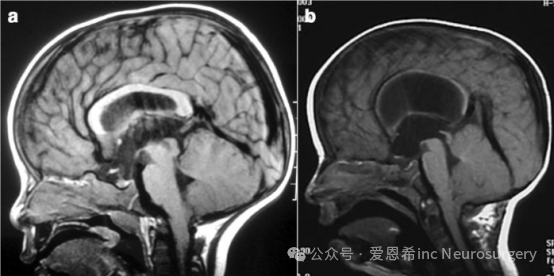

两张矢状位 T1 磁共振成像(MRI)显示三脑室脑积水及小脑扁桃体轻度下移的类似图像。然而,在 a 图中,小脑容纳于正常的后颅窝(PCF)内,尽管其脑积水的严重程度低于 b 图,但仍可推测脑积水(导水管狭窄)在此情况下导致了小脑扁桃体下疝(CIM)。相反,在 b 图中,小脑位于较小的后颅窝内(观察穹窿向上疝出,伴 Galen 静脉系统移位),且导水管通畅;因此,很可能在这种情况下 CIM 导致了脑积水。